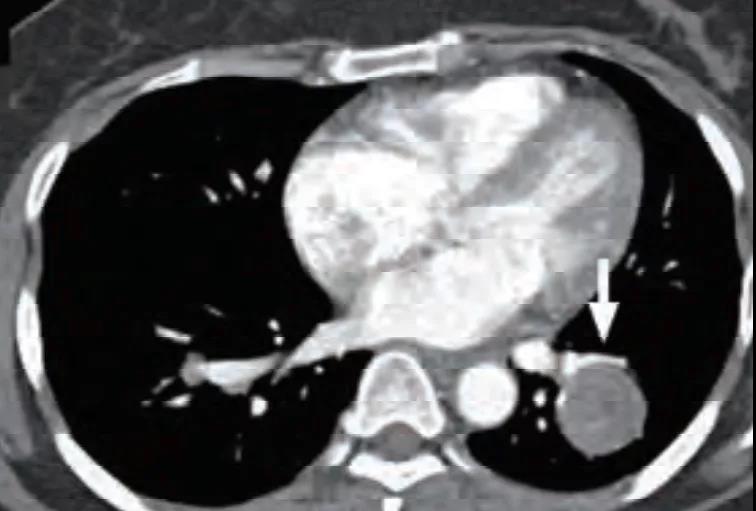

可见特征性血管贴边征(图 2)和周围血管包绕征,即增强动脉期见病灶边缘明显强化的点状血管断面